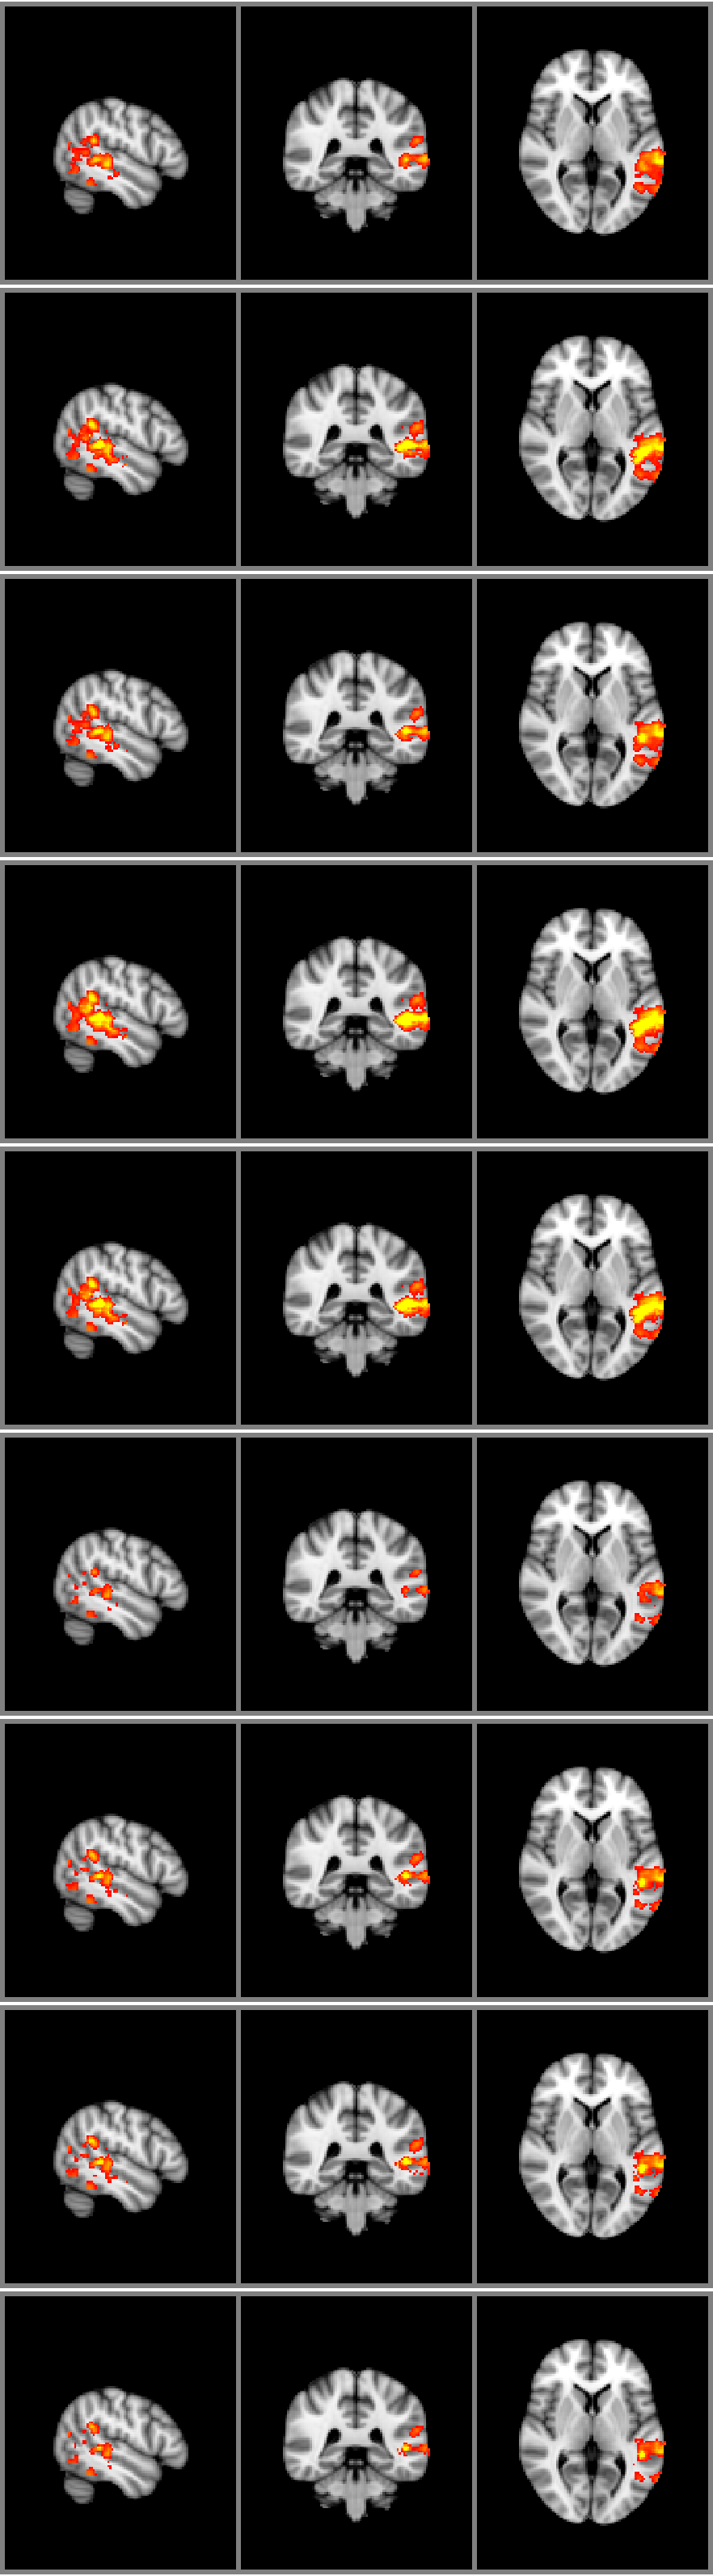

Refer to caption

Figure 5: Posterior probability of in favour of a linear increase in activation with MMSE.

The difference in evidence is that obtained from that of the entire brain model. However, the evidence of the full brain model can be decomposed into independent and voxel-wise contributions if the Markov random field is fixed at its best estimate. Hence, we can ask the very interesting question as to where the non-linear interpolation model outweighs the linear model? Figure 5 shows the posterior probability in favour of the linear model. Bright/positive values here indicate evidence in favour of the simpler, linear model while darker/red values indicates a higher probability in favour of the exponential covariance function GP.

The figure clearly shows an overwhelming tendency towards a nonlinear description of the dependence of image features with MMSE. The largest evidence in favour of the linear model is in the superior and middle temporal gyrus as well as in the occipital regions. The evidence for the two models in the temporal lobe is 243×103243superscript103-243\times 10^{3} and 505×103505superscript103-505\times 10^{3}, respectively for the squared exponential and linear GP. This suggest that for the left temporal lobe in particular the non-linear model is still a better model. However the evidence in favour of the model has dropped to a factor of only 222 per voxel. Thus, the measured activity in the temporal lobe depends almost monotonically with the MMSE scores.